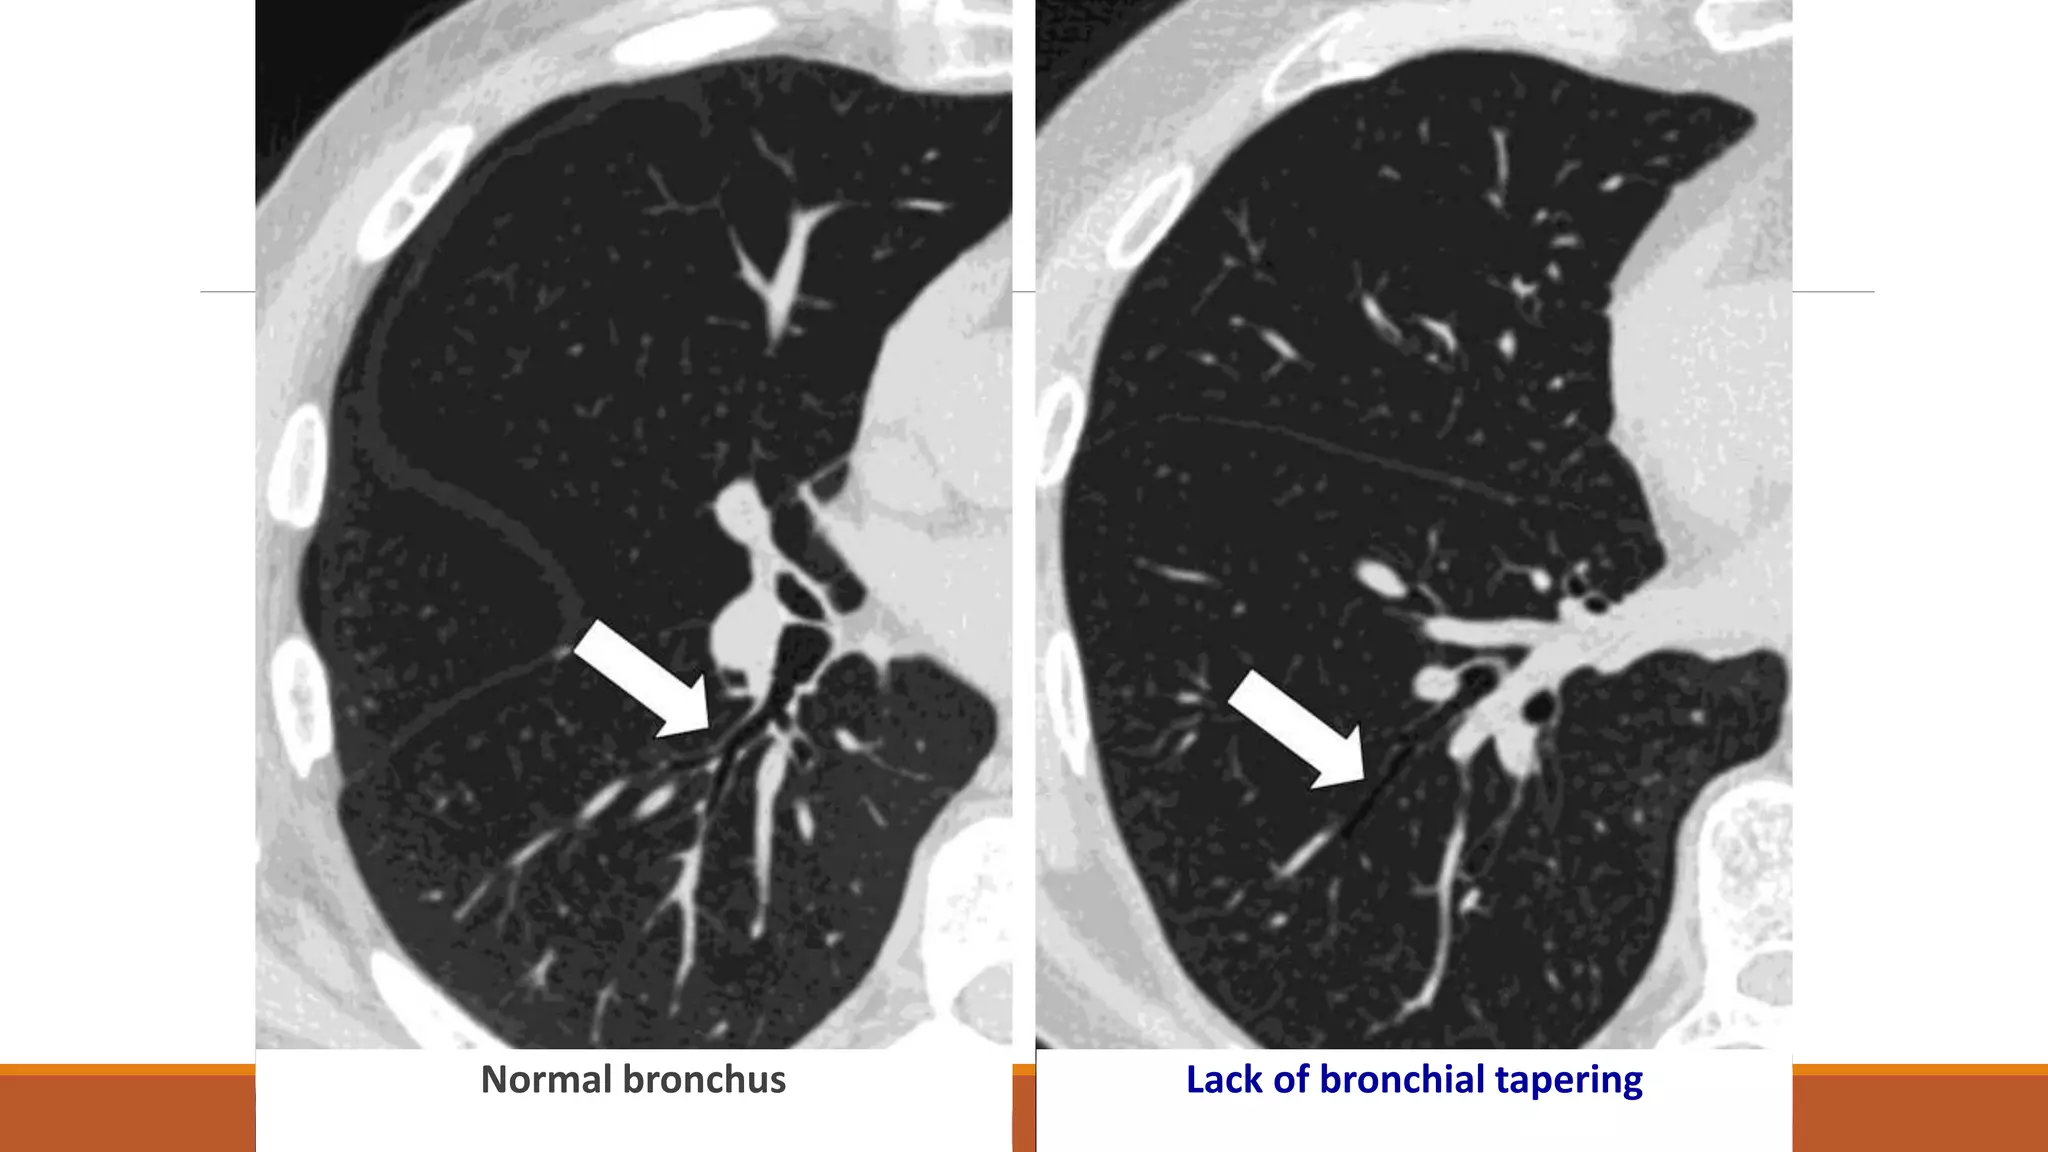

•Signet ring sign (broncho-arterial ratio > 1).

•Lack of bronchial tapering.

•Abnormal bronchial contour.

•Visibility of peripheral air ways.

Signet ring sign

broncho-arterial ratio > 1

Normal bronchus Lack of bronchial tapering

Abnormal bronchial contour

Visibility of peripheral air ways within 1cm

from the costal pleura